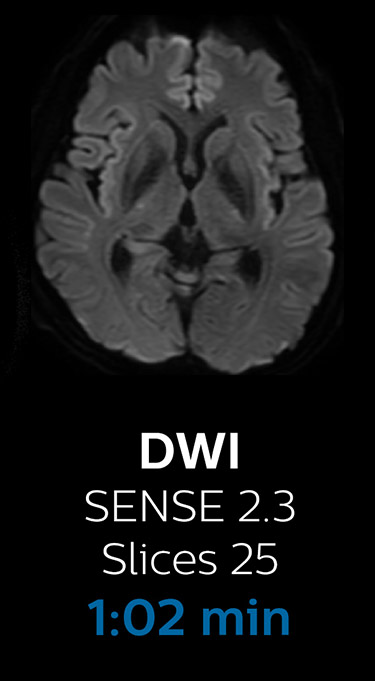

Scanning time reduction in brain MRI with Compressed SENSE

Fast MRI of brain

With Compressed SENSE, the scan time for the routine brain examination at KNC was reduced from 15:48 to 10:19 minutes, which corresponds to 35% reduction.

Ingenia 3.0T CX

Scan time 15:48 min.

Brain with Compressed SENSE

Ingenia 3.0T CX

Scan time 10:19 min.